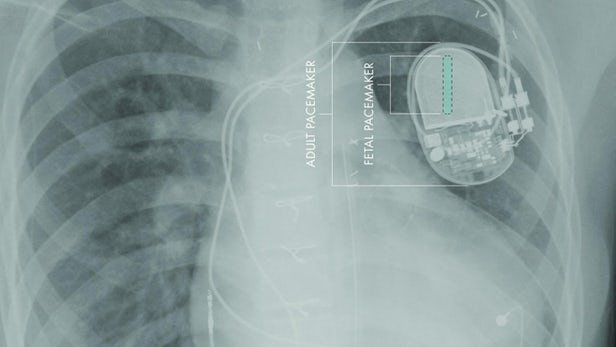

به گزارش ایسنا و به نقل از ساینسنیوز، دستگاه ضربانساز قلب جنین با کمتر از چهار میلیمتر قطر برای قرارگیری در شرایط استریل بدون آسیبرسانی به اندامهای درونی مادر و جنین طراحی شده است.

دستگاه ضربانساز جنین تنها از هفت بخش ساخته شده که با قرارگیری هوشمندانه با استفاده از ابزار اختصاصی برای جراحی جنین از طریق سرویکس به درون رحم منتقل میشود.